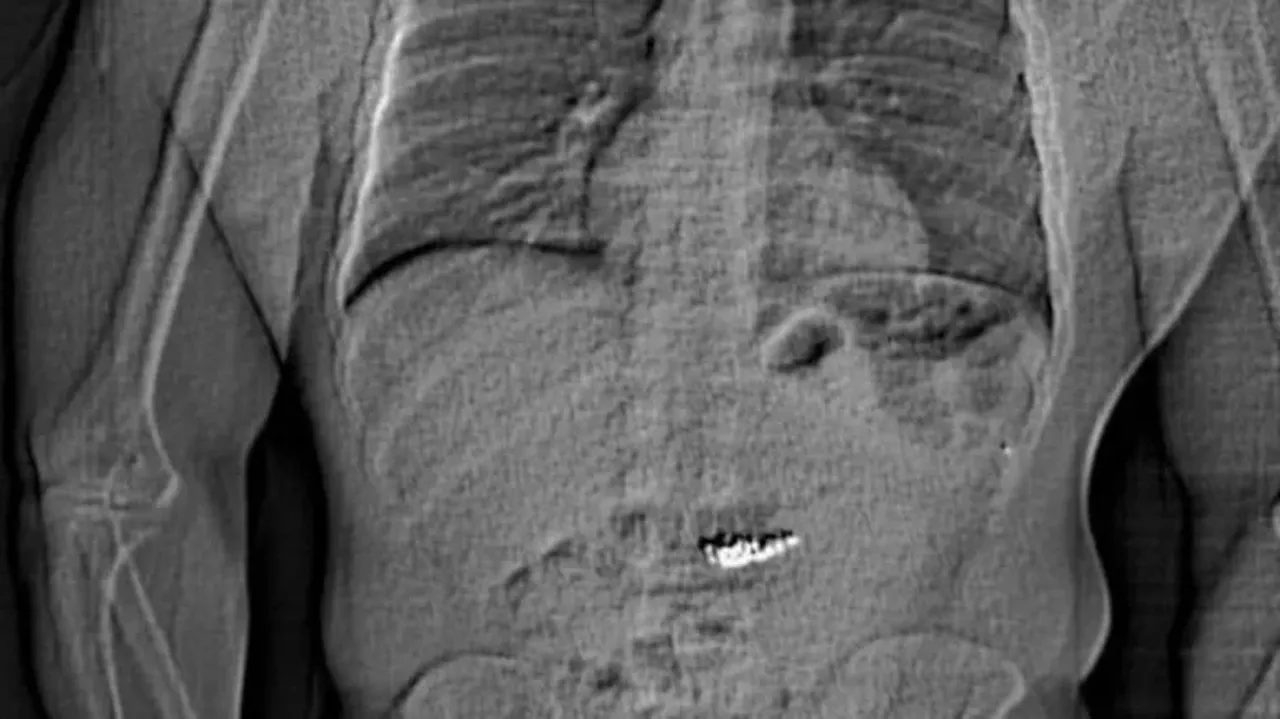

Orlando polisi, hırsızın peşine düştü ve aracıyla kaçarken kısa sürede yakalamayı başardı. Hırsızın röntgen muayenesinde çaldığı küpelerin midesinde olduğunun tespit edildi. Günlerce hastanede tutulan hırsızın vücudundaki küpeler doğal yollarla çıkarıldı.